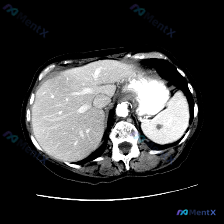

整理了一份有点意思的读片分析,核心是“关注点错位”——临床问的是脾脏病变,但影像的真正异常在肝脏。 一、先看影像基础信息 - 序列:腹部MRI轴位T1加权像 - 覆盖范围:上腹部(肝左/右叶部分、脾脏、胰腺体尾、胃泡、腹主动脉) - 图像质量:信噪比良好,无明显运动伪影 二、关键影像表现(按事实优先...

看到一份腹部MRI的读片资料,病灶在脾脏,整理一下思路分享给大家。 病例影像核心信息 - 影像类型:腹部MRI T2加权序列(T2WI),轴位 - 主要发现:脾脏边缘可见数个小类圆形高信号灶(点状高亮),呈水样信号,边界锐利、边缘光整 - 其他结构:肝实质信号相对均一,未见明确占位;胰腺体尾部形态、...

最近看到一份读片资料,提问是“观察脾脏病变”,但仔细看完影像和分析后,觉得这个病例的思维转折比诊断本身更有价值,整理一下思路和大家分享。 --- 先看核心影像事实(基于MRI-T2轴位) 这份图像的基本信息很明确:上腹部轴位T2加权像,有轻度呼吸伪影但不影响评估。 直接说关键的阳性/阴性发现: ✅...

今天整理了一个很有意思的“反向”影像分析案例,核心不是鉴别病变性质,而是先搞清楚“病变到底存不存在”——这个前提如果错了,后面的分析全是浪费时间。 先看一下当前的资料 临床提示:脾脏病变 影像资料:单帧腹部MRI T2序列轴位图像 影像客观描述: - 肝脏:轮廓尚可,实质信号基本均匀,未见明确局灶性...

整理了一份脾脏占位的读片+分析思路,感觉这个病例的「混杂信号」挺有代表性,容易被带偏,分享出来一起理一理。 --- 一、先看影像核心表现 这份是上腹部MRI轴位T2加权像: - 肝脏、胃壁、腹膜后大血管这些都还好,没见明显异常; - 脾脏形态正常,但里面有一个类圆形占位,边界尚清; - 关键信号:T...